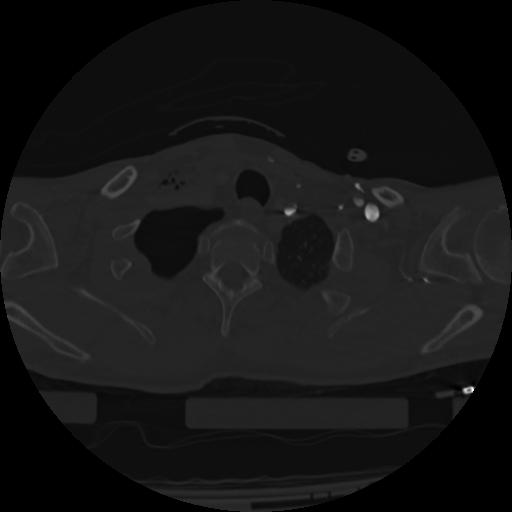

22 ANGIO,CE,Vol,0.5,ANGIO,,